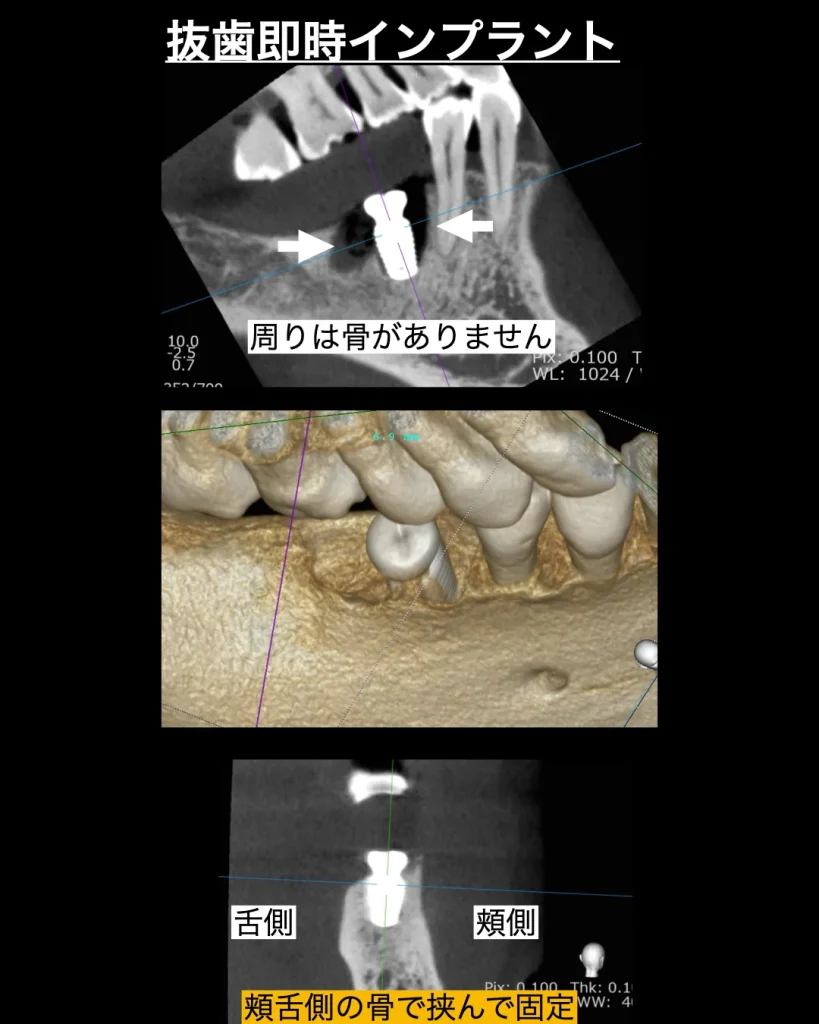

患者様は右下の奥歯が噛むと痛いという理由で当院を来院されました。レントゲンを撮影すると歯根が真っ二つに破折しており、膿もあり、周りの骨が大幅に溶けてしまっていました。診断の結果、幸いにもインプラントを支えることができる骨が一部分だけ残っていたので、抜歯してその日にインプラントを埋入する「抜歯即時インプラント」をご説明させていただきました。患者様は治療ができるだけ痛くなく、早く終わる抜歯即時インプラントの説明に納得され、インプラント治療を開始しました。

手術当日は、破折した歯を周りの歯茎を傷つけずに丁寧に、繊細に抜歯します。そして、インプラント窩をドリルで形成し、一部分残っているわずかな骨を利用しインプラントを固定しました。初期固定は強くとれ、インプラントを維持できたので、キャップ(歯茎を治すためのキャップ)をいれ、周りに少々の骨補填材とコラーゲンを挿入し治療を終了しました。